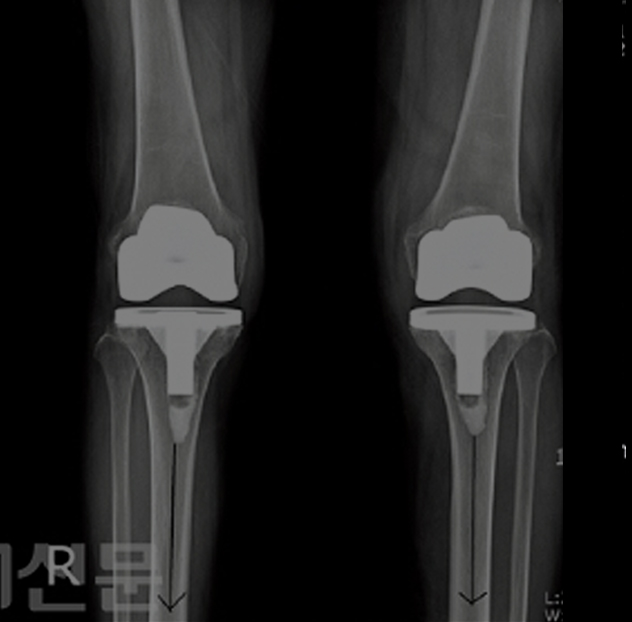

전후사진

서재곤 링커병원 전후사진을 확인해 보세요.